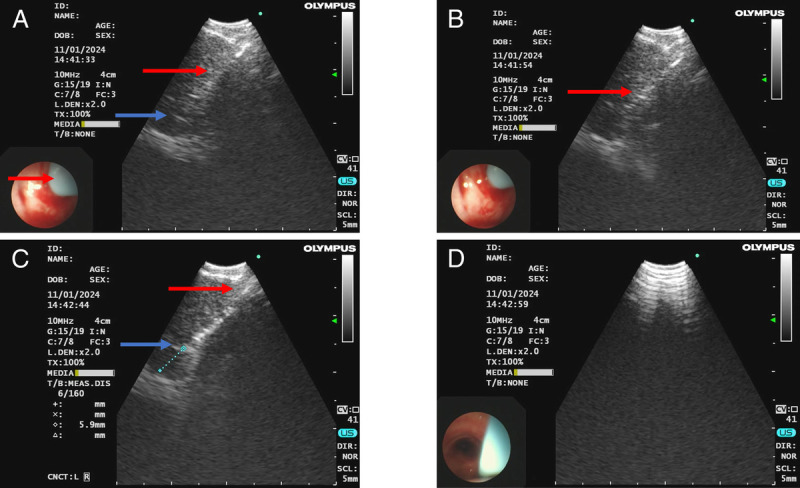

Endobronchial ultrasound-guided transbronchial tunnel Cryobiopsy for mediastinal lymphadenopathy (with video).

超声引导下经支气管隧道低温活检治疗纵隔淋巴结病(附视频)。